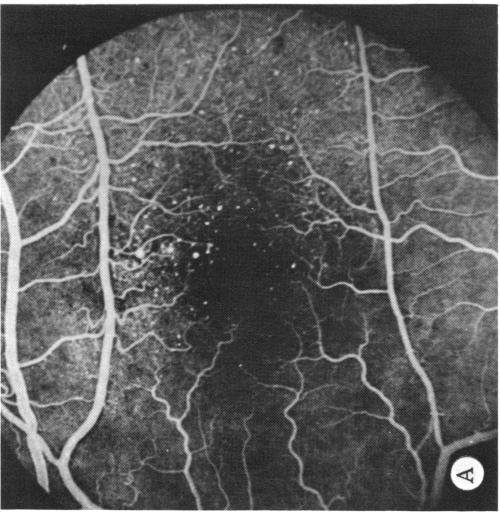

Coats' disease and congenital vascular retinopathy.

Trans Am Ophthalmol Soc. 1976;74:365-424.